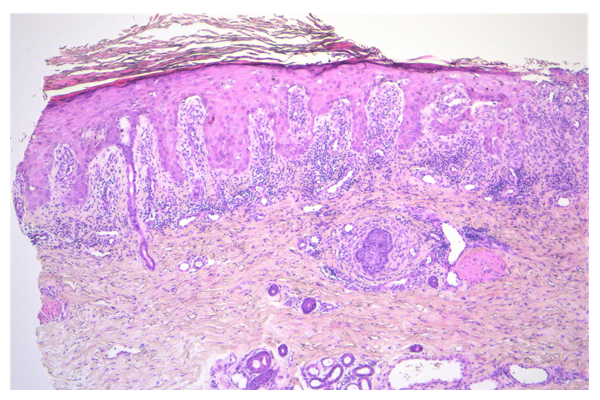

Doente do sexo feminino de 62 anos com doença renal crónica, foi referenciada por úlceras cutâneas dolorosas no lábio inferior, coxa,...